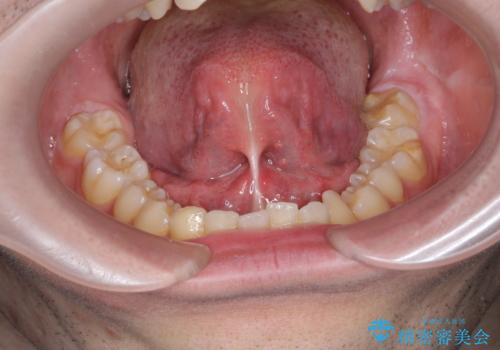

滑舌の改善 舌小帯の形成

- 舌の動きが悪く滑舌の改善を求めて来院されました。

静脈内鎮静下で、ほとんど記憶のないうちに手術を行い滑舌の改善を計画します。

舌小帯の形成を行うことで、動きがよくなり滑舌の改善を喜んでいただくことができました。